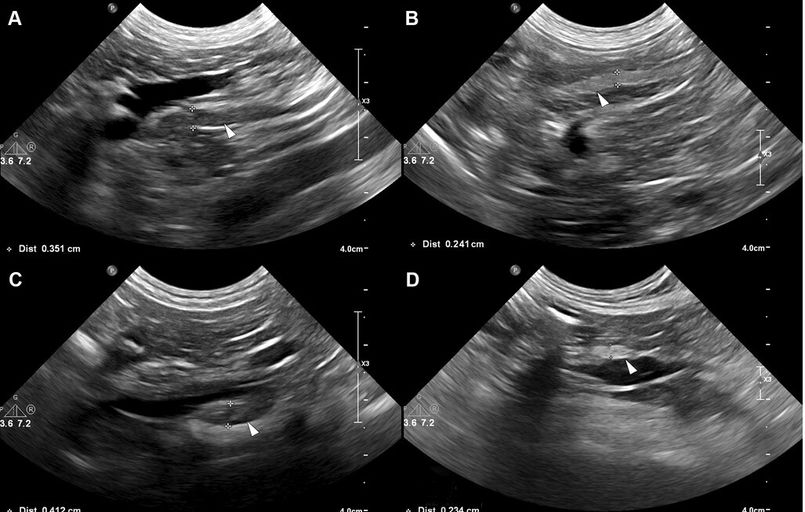

Veterinary Radiology & Ultrasound, 2003